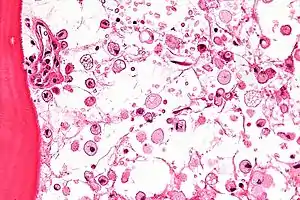

Micrograph showing crinkled paper macrophages in the marrow space in a case of Gaucher disease, H&E stain.

The disease is caused by a defect in housekeeping gene for lysosomal glucocerebrosidase (also known as beta-glucosidase, EC 3.2.1.45, PDB: 1OGS) on the first chromosome (1q22). The enzyme is a 55.6-kilodalton, 497-amino acid-long protein that catalyses the breakdown of glucocerebroside, a cell membrane constituent of red and white blood cells. In Gaucher disease, the enzyme is unable to function correctly and glucocerebroside accumulates. The macrophages that clear these cells are unable to eliminate the waste product, which accumulates in fibrils, and turn into 'Gaucher cells', which appear on light microscopy to resemble crumpled-up paper.[3]

A diagnosis can also be implied by biochemical abnormalities such as high alkaline phosphatase, angiotensin-converting enzyme, and immunoglobulin levels, or by cell analysis showing "crinkled paper" cytoplasm and glycolipid-laden macrophages.